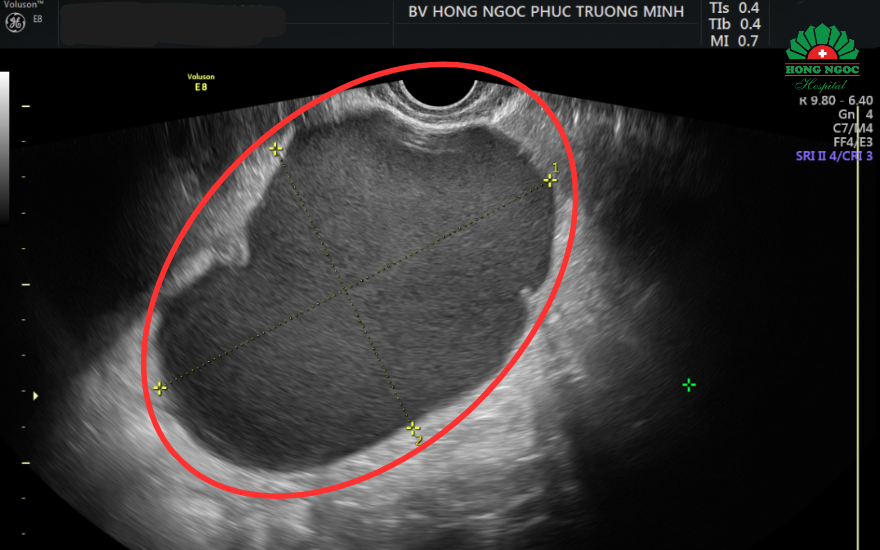

Sau khi thăm khám và siêu âm, bác sĩ phát hiện chị H có một khối u kích thước 10x13cm ở buồng trứng phải, nghi ngờ bên trong có nhiều máu đông, dấu hiệu điển hình của u nang socola, có nguy cơ ảnh hưởng tới sức khỏe và khả năng sinh sản.

Kết quả thăm khám và siêu âm cho thấy khối u nang lớn có kích thước lên tới 10x13cm.